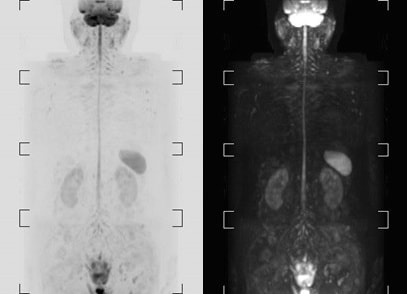

院長のDWIBSです。異常な高信号域がなく、ほっと⼀安心。

院長は家族歴に膵癌があり膵癌発症リスクが高いものの、一般的な検査である超音波は精度が高いとは言えません。そんな場合にDWIBSが効果を発揮します!